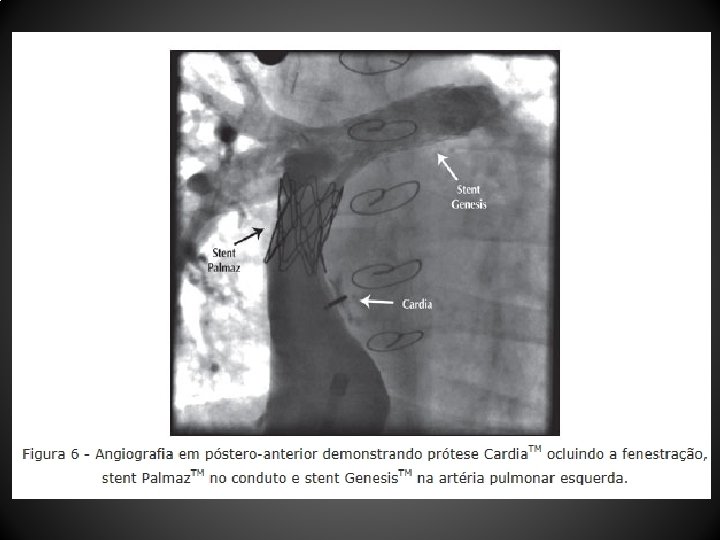

Resultados • Entre abril de 2004 e dezembro de 2010, 12 pacientes (média de idade, 103, 1 + 88, 6 meses; peso, 29, 9 + 12, 7 kg) submetidos a CF (10 tubos extracardíacos, 2 túneis intra-atriais) foram tratados 44, 1 + 26, 7 meses após a CF • Um paciente não tolerou o teste de oclusão com o balão, sendo contraindicado o procedimento • As próteses utilizadas foram: Helex. TM (4 pacientes), Amplatzer. TM (2 pacientes), Cardia Atriasept. TM (2 pacientes), Figulla. TM (1 paciente), Cera. TM (1 paciente), e 1 stent coberto Cheatham-Platinum. TM • Após a oclusão da fenestração, a saturação de oxigênio aumentou significativamente (82, 1 + 6, 5% para 95, 2 + 3, 2%), sem aumento significativo da pressão venosa central (12, 4 + 2, 6 mm. Hg para 14, 5 + 2, 3 mm. Hg) nem queda do débito cardíaco • Após o procedimento foi observado shunt residual imediato em 5 pacientes, que desapareceu antes da alta